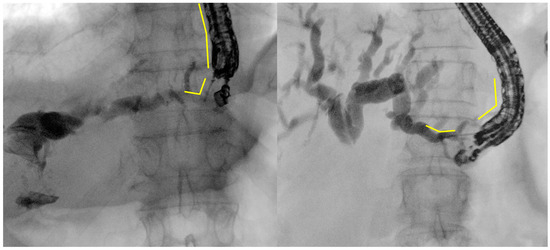

- Tract dilation

- Stent positioning